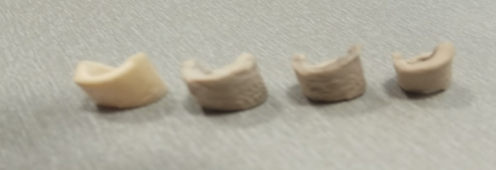

Boli navrhnuté ďalšie konštrukčné riešenia iných implantátov na mieru, ktoré boli následne vyrobené. Jednalo sa o modely skúšobných anatomických náhrad na mieru – segmentov skeletu králika určených na predklinické testovanie v rámci prípadových štúdií. V rámci modelovania a výberu materiálovej kompozície sa počítalo s implementáciou prítomnosti markerov na základe translucencie materiálu PEEK.

Obr. 2 Implantát vyrobený na mieru pre predklinické testovanie v rámci animálnych prípadových štúdií